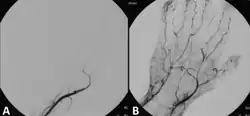

A Doppler evaluation is often the first imaging choice to diagnose ALI because it is inexpensive, accessible, non-invasive, and can be done in a short amount of time.[2] It is used to show the extent and severity of the ischaemia by showing flow in smaller arteries. An occlusion of the artery would be seen by decreased or absent flow distal to the occlusion. Doppler ultrasound can even distinguish between embolic and thrombotic plaque. The former would show a delineated, round thrombus, whereas the latter would show narrowed arterial lumen with atherosclerotic plaque.[2]

Although Doppler ultrasounds provide excellent information, there may be difficulty in evaluating aortic or iliac arteries in patients who are obese or have significant gas.[2] Other diagnostical tools are duplex ultrasonography, computed tomography angiography (CTA), and magnetic resonance angiography (MRA). The CTA and MRA provide higher-resolution images used in planning revascularization, but they may only be used in patients without a threatened limb due to time constraints. CTA uses radiation and may not pick up on vessels for revascularization that are distal to the occlusion, but it is much quicker than MRA.[1] In treating acute limb ischaemia, timing is everything.[18]

Endovascular intervention

Endovascular interventions for ALI are minimally invasive procedures designed to quickly restore blood flow and avoid more extensive surgery. In endovascular interventions, a catheter is used to deliver medication such as thrombolytics to dissolve the clot. In the past, streptokinase was the main thrombolytic chemical. More recently, drugs such as tissue plasminogen activator, urokinase, and anistreplase have been used in their place. Mechanical methods of injecting the thrombolytic compounds have improved with the introduction of pulsed spray catheters—which allow for a greater opportunity for patients to avoid surgery.[21][22] Pharmacological thrombolysis requires a catheter to be inserted into the affected area, attached to the catheter is often a wire with holes to allow for a wider dispersal area of the thrombolytic agent. These agents lyse the ischemia-causing thrombus quickly and effectively.[23] However, the efficacy of thrombolytic treatment is limited by hemorrhagic complications. Plasma fibrinogen level has been proposed as a predictor of these hemorrhagic complications. However, based on a systematic review of the available literature until January 2016, the predictive value of plasma is unproven.[24] After the clot has been dissolved or removed, a stent or balloon may be placed to keep the artery open and prevent further ischemia.